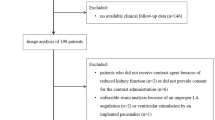

Over 375 consecutive patients evaluated and followed at the HCM Competence Center from February 2007 to November 2014, 217 HCM patients were enrolled and included in this study. The reasons for exclusion have been presented in a flow chart (Fig. 1).

The mean age on initial evaluation was 50.1 ± 15.6 years, and 146 (67%) were male. Demographic and clinical characteristics of the population (n = 217) are presented in Table 1. The median follow-up duration was 2.8 ± 1.5 years.